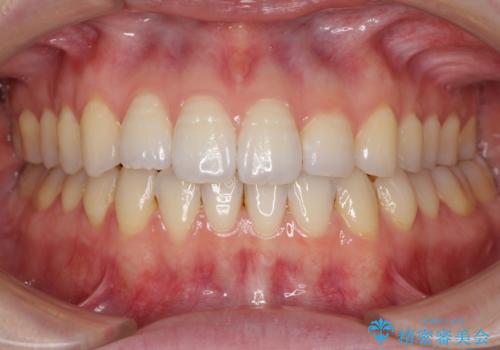

IPR(歯と歯の間を削る処置)によりスペースを獲得して上下顎前歯のデコボコを改善し、前歯が前方に突出しないように設定した上で、インビザラインにて矯正治療を行うこととしました。

途中体調を崩され、長い期間矯正治療を休むことになったため4年半ほどの治療期間がかかりました。